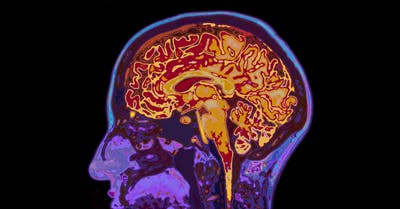

最複雜的運算都發生在大腦皮質,一般來說,大腦就是個大型神經網路集中地,從接收外部資訊到做出反應,一群神經元的協同運算才能完成一項功能,所以鳥類對於空中飛行有極高的理解能力,有些動物還能自行精準導航好幾公里,大腦都採用了類似的運算模式。而在人類大腦皮質中,科學家發現一處組織比其他動物還厚,研究人員更在人類皮質深層發現,人類單一神經細胞其實可以做到過去認為需要許多神經元協同才能做的運算。

這篇在 Science 雜誌發表的論文顯示,人類的腦可以調控電流的幅度來提升訊號的持續長度和效果。這讓單一神經元可以做更多事,比如這裡提到的 XOR 運算(邏輯互斥或),之前普遍認為需要更多神經元合作,其實可以單靠一顆神經元辦到。